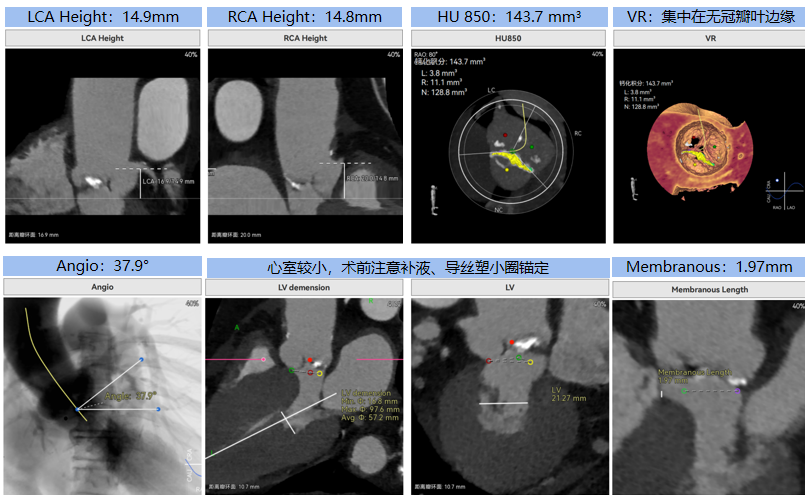

病例概览

患者病史 体检发现心脏瓣膜病半月余,平素无症状 ,有高血压病史。 后来院复查诊断为:主动脉瓣狭窄(重度)、先天性主动脉瓣二叶瓣畸形、心室肥厚、升主动脉扩张心功能 I 级(NYHA 分级)、高血压病 2 级(极高危)。 术前 CT:Type0型二叶瓣,瓣叶增厚,无钙化,类风湿性;瓣环径25.6mm,LVOT稍收窄,瓣环水平夹角66.6°,轻微横位心;左右冠开口高度可,瓣叶不长,无冠脉风险;心室收缩末内径约32mm,室壁增厚;外周入路无明显迂曲,无钙化、双侧内径可、双股中分叉,右侧为主入路能够支持20F大鞘通过。 造影角度及入路:LAO 6° CAU 13° 手术策略 采用右侧股动脉为主入路,左侧为辅助入路,常规穿刺。推荐使用20球囊预扩,预装TAV29瓣膜,初始定位对齐瓣环上0mm开始释放。 手术过程 20号球囊预扩无明显腰征 输送器过弓跨瓣顺滑 80%工作位观察 术后造影,瓣膜释放位置良好,无瓣周漏 术后超声:人工生物瓣释放后形态满意,瓣叶开放、关闭活动良好,无瓣周漏;跨瓣血流速度降至 2.5m/s,平均压力梯度6mmHg,符合手术预期。 Prostyle A®预装干瓣——“刚柔并济”助力临床最优化解决方案: 丝滑过弓能力:Prostyle A®短瓣架设计联合远端超滑亲水涂层,即使没有联合使用snare,都可以柔顺过弓,该例横位心的患者更好的展现了输送系统的柔顺性; 平衡的径向支撑力:该例患者Type0型二叶瓣,术后形态展开良好且无瓣周漏,在横位心等复杂情况下实现稳定锚定。 80%可回收设计:80%工作位观察,起搏时间更短,对患者损伤减少到最小,也利于术中精准调整瓣膜位置,保证术后效果。